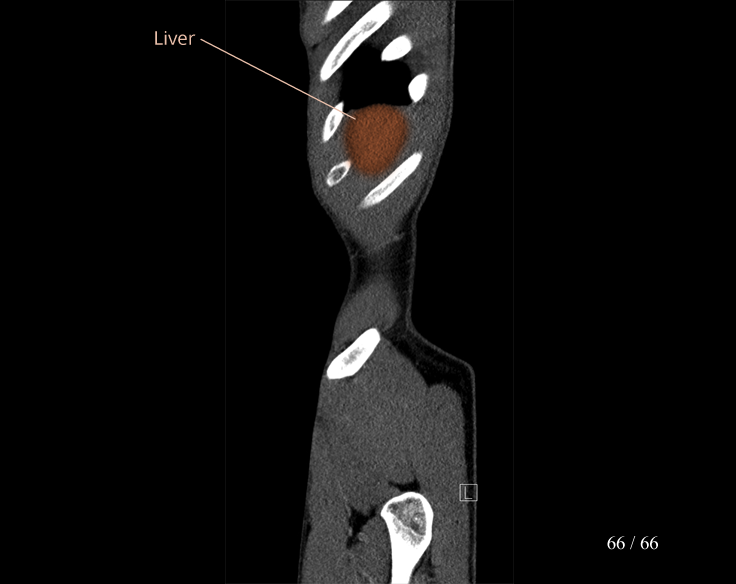

Body

Covers abdominal CT anatomy.